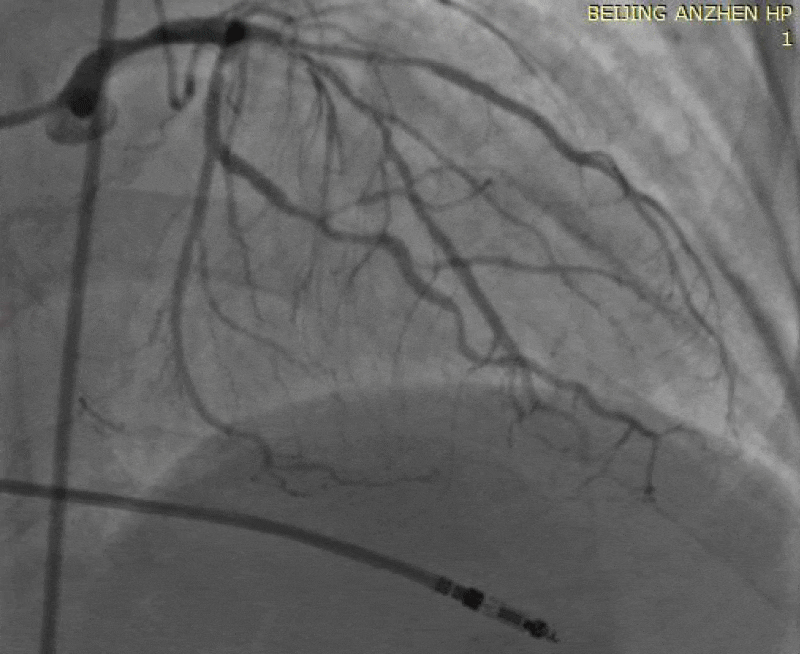

Five hours later, the patient suddenly developed chest pain accompanied by sweat and pale, with blood pressure of 150/70mmHg. The patient was given ECG monitoring, oxygen inhalation and intravenous access. Seventeen minutes later, the patient experienced loss of consciousness and ECG showed ventricular fibrillation. The patient recovered consciousness after defibrillation and simple ventilator assisted breathing, blood pressure was 80 / 50mmHg, then the patient was turned into the cath lab for emergency PCI. After the patient entered the cath lab, ventricular fibrillation occurred again. Defibrillation treatment was performed for the second time, the patient received PCI treatment under continuous chest compression. After puncturing the right femoral artery, the 6F JL4.0 guiding catheter was placed at the LCA opening, coronary angiography showed LCX occluded, LAD still had blood flow. Runthrough guide wire was sent to the distal LCX, another Runthrough guide wire was sent to the distal LAD, the Medtronic 2.5mm × 15mm balloon was carried retracement, coronary angiography showed the mild LCX hematoma extension made LCX occluded, Medtronic 2.5mm×15mm balloon was dilated at 8-10atm from the proximal LCX to the LCX stent, coronary angiography showed that the blood flow of LCX recovered. Then puncturing the left femoral artery, intra-aortic balloon pump (IABP) balloon was implanted into the descending aorta, heart rate restored to 40 times per minute. Then the operator sent PACEL temporary pacing catheter to the right ventricular apex, the patient received temporary pacing therapy with frequency of 80 times per minute. During the treatment, the patient was given intravenous injection of 1mg epinephrine and 1mg atropine, and was given intravenous drip of 5% sodium bicarbonate, blood pressure was remained at 80-100mmHg, about 20 minutes later the patient recovered spontaneous cardiac rhythm, blood pressure rose to 80-120/40-70mmHg. Coronary angiography showed the blood flow of LAD and LCX restored. Considering possible hematoma extension of the LCX, the Medtronic 2.25mm×18mm stent was placed into the proximal LCX with the inflation pressure of 10atm, the LEPU 2.75mm×18mm stent was placed into the proximal LAD with the inflation pressure of 14atm, the LEPU 3.5mm×15mm stent was placed from LM to LAD with the inflation pressure of 18atm, the angiography showed that all stents achieved good apposition to the wall, the blood flow was TIMI-3, there was no hematoma and dissection. The LCX opening was mild involved, considering the possibility of dissection may occur, so we did not perform kissing dilation. After operation the patient was transferred to the CCU ward for further treatment Figures 1-4.

Figure 3:

Figure 4: